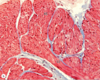

Skeletal Muscle

F - Fibroblast nucleus

A - A band

I - I band

N - Muscle nuclei

Skeletal Muscle